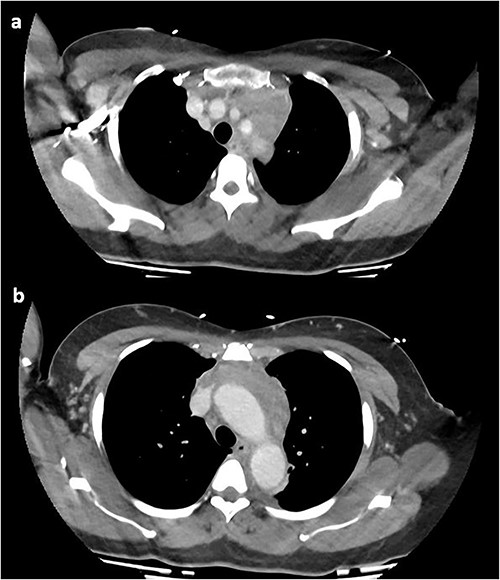

At this time, the mass was suspicious for a malignancy, possibly a thymoma, lymphoma or germ cell tumour. All serum tumour markers (AFP, CEA, CA19-9, CA125) were negative. FDG-PET demonstrated that the anterior mediastinal density had moderate FDG update and no other avid lesions elsewhere. After multidisciplinary discussion, the mediastinal density was thought to most likely represent left brachiocephalic venous thrombophlebitis. A dedicated computed tomography (CT) venogram was performed, demonstrating extensive UEDVT from the left internal jugular vein extending into the left brachiocephalic and subclavian veins, seen in Fig. 3.

CT venogram demonstrating UEDVT in left brachiocephalic vein in the (a) upper chest and (b) lower chest.